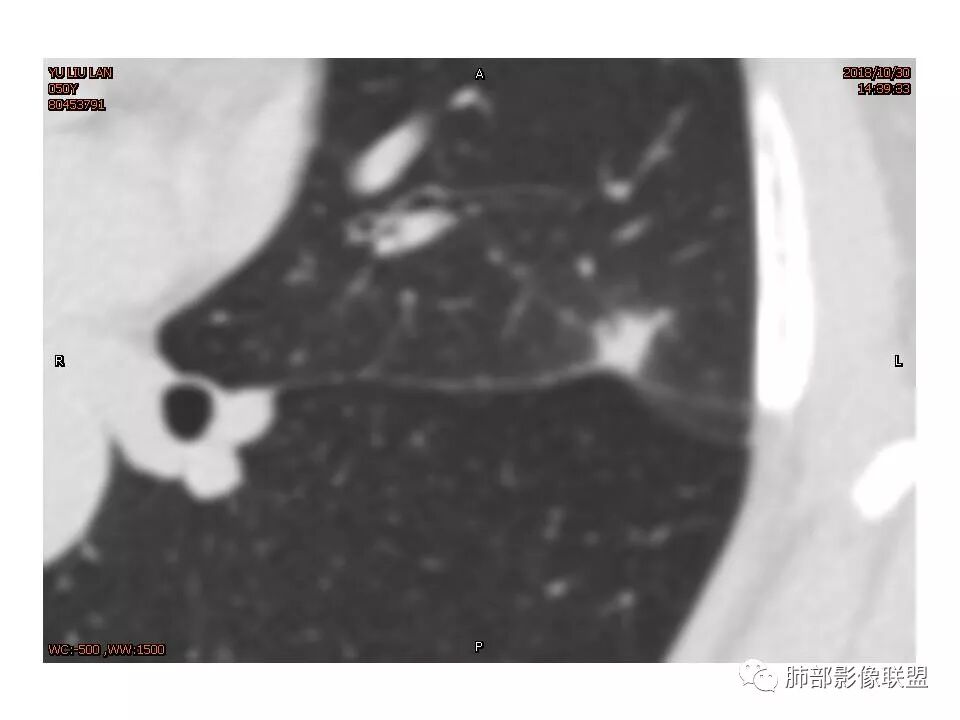

左肺上叶结节,部分边缘膨隆,边缘毛刺,斜裂牵拉,增强中度强化,血管穿行,血管略增粗。考虑肺癌,腺癌可能性大,鉴别肉芽肿性炎

左肺上叶结节影,病灶周围呈磨玻璃样改变边缘见毛刺、分叶及胸膜牵拉,增强扫描病灶明显强化,病灶未跨叶间裂,考虑炎性病变,待除外小腺癌。

炎性征象多,平直,长毛刺,尖角征,周围晕模糊,炎性病变放前,腺癌待删,抗炎后复查

左上肺结节 周围磨玻璃边缘模糊 结节周围有短及长毛刺 虽有收缩力 但病变边缘收缩较多 长毛刺对邻近外侧胸膜没什么收缩 增强有延迟强化 进入血管稍增粗 首先考虑炎性 感觉炎症吸收过程中也可以这样 腺癌待排

细小毛刺,梳状平行,周围边缘模糊晕,血管未收侵犯,支气管未见牵拉扩张,多条淋巴道与胸膜相联,倾向于炎性病变

女性,50岁。U型凹陷、平直征

南边:支持炎性

我倾向于炎性结节,癌待排

1.胸膜下略不规则实性密度结节影,孤立,缺乏典型深分叶,可见淡薄边界模糊磨玻璃晕,可见相对细长软毛刺。

2.如南边老师分析,病灶缺乏边缘膨隆优势,甚至部分平直内收。

3.病灶收缩力不强,整体强化程度不显著。

4.综上,病灶更符合炎性,如隐球菌感染等,而不大符合肺腺癌。具体到机化性肺炎略有些出乎预料。